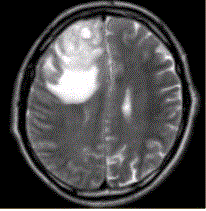

问题 患者女,67岁,头痛伴呕吐1周。既往体健。MR表现如下图。 关于多形性成胶质细胞瘤,描述正确的是

选项 A.儿童青少年常见 B.好发于额、颞叶大脑灰质及白质区 C.CT平扫密度均匀 D.增强检查均匀强化 E.瘤周水肿轻微,占位效应显著

答案 B